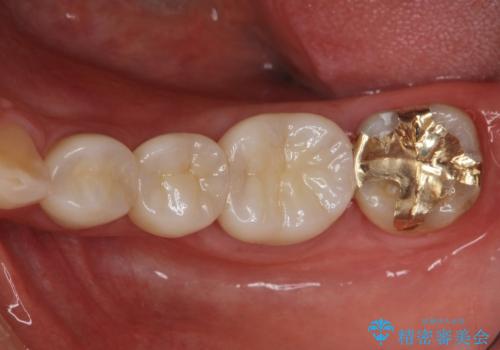

- 26万円(仮歯・ファイバーコア・フルジルコニアクラウン×3) 費用は治療当時の料金となります